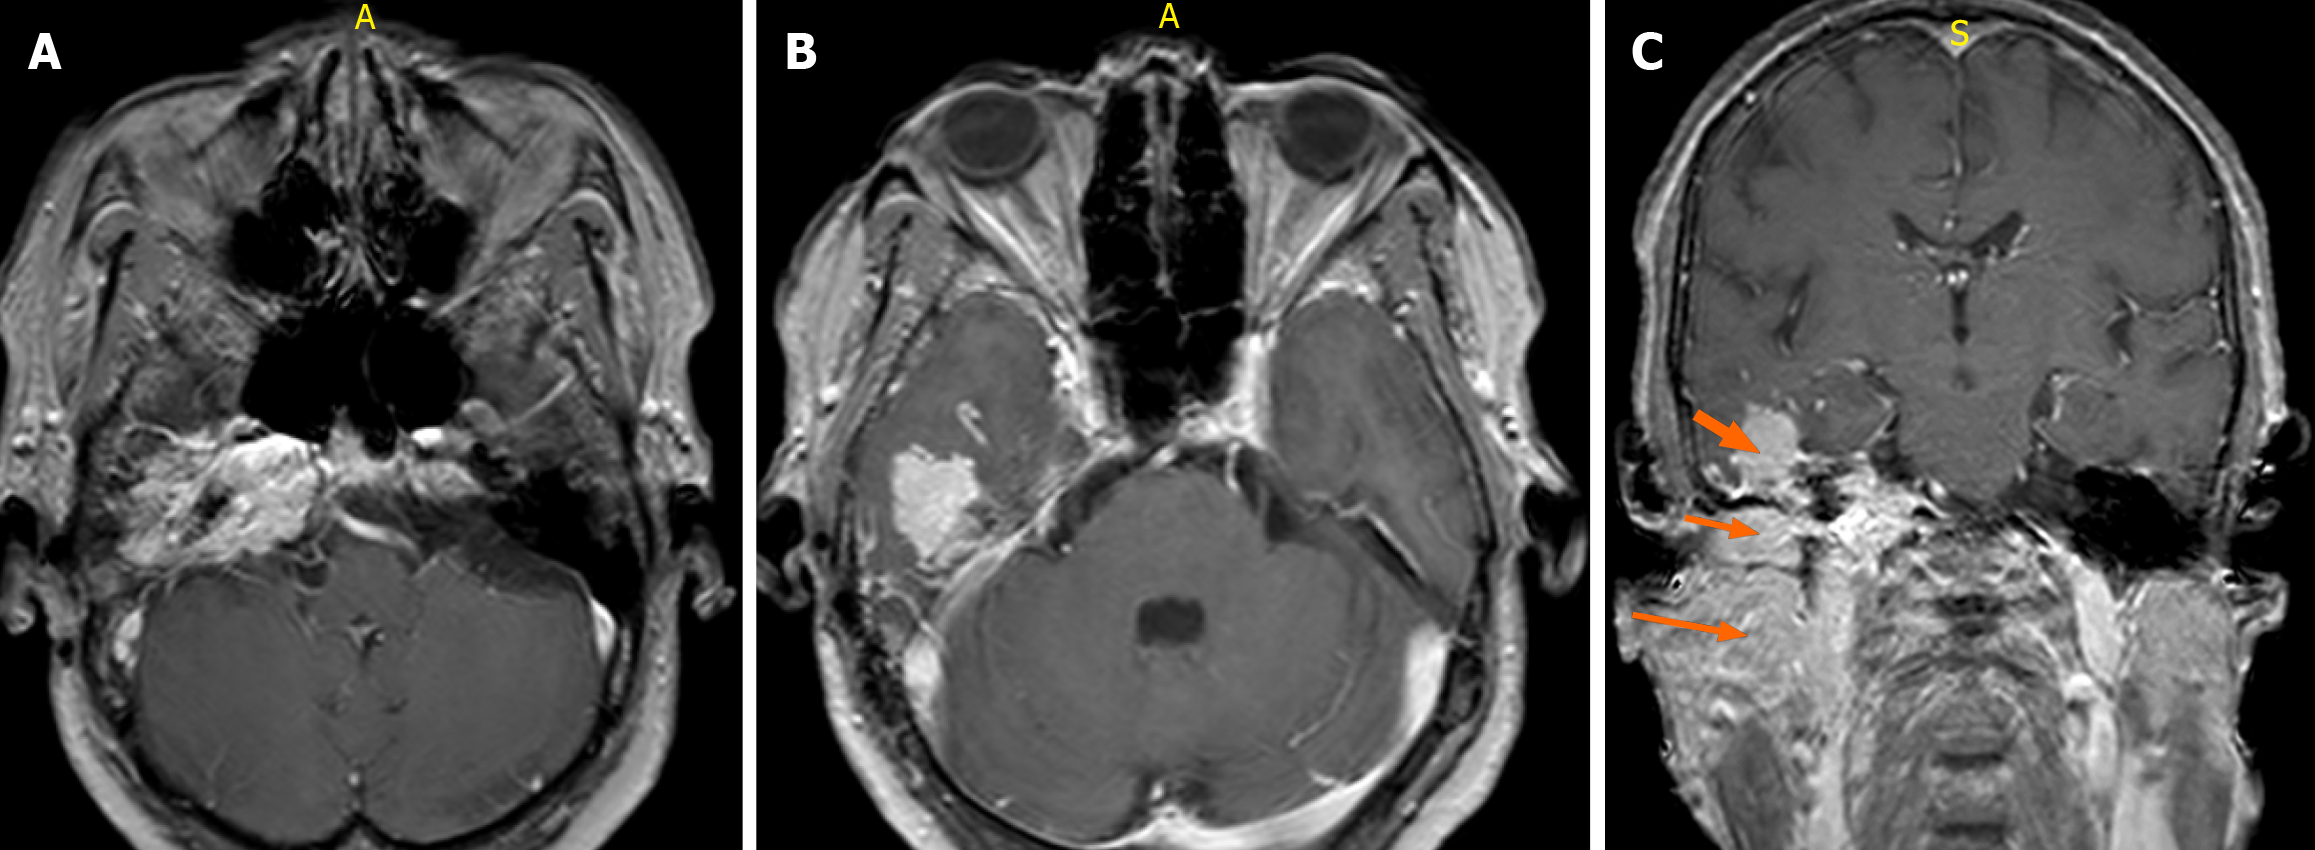

Figure 5 Contrast-enhanced magnetic resonance imaging features of the right jugular foramen mass.

A and B: Axial gadolinium-enhanced T1-weighted fast field echo (FFE) magnetic resonance imaging (repetition time 500-700 milliseconds, echo time 10-20 milliseconds, flip angle 20°-30°, slice thickness 3 mm) following intravenous administration of gadolinium-based contrast (0.1 mmol/kg) demonstrates avid enhancement of the lesion involving the right jugular foramen, middle ear cavity, and ipsilateral temporal lobe; C: Coronal T1-weighted FFE post-contrast image shows an intensely enhancing mass in the right jugular fossa with superolateral extension into the ipsilateral inferior temporal lobe (short thick arrow), inferior extension into the ipsilateral middle ear cavity (short thin arrow), and further spread into the masticator space (long arrow).